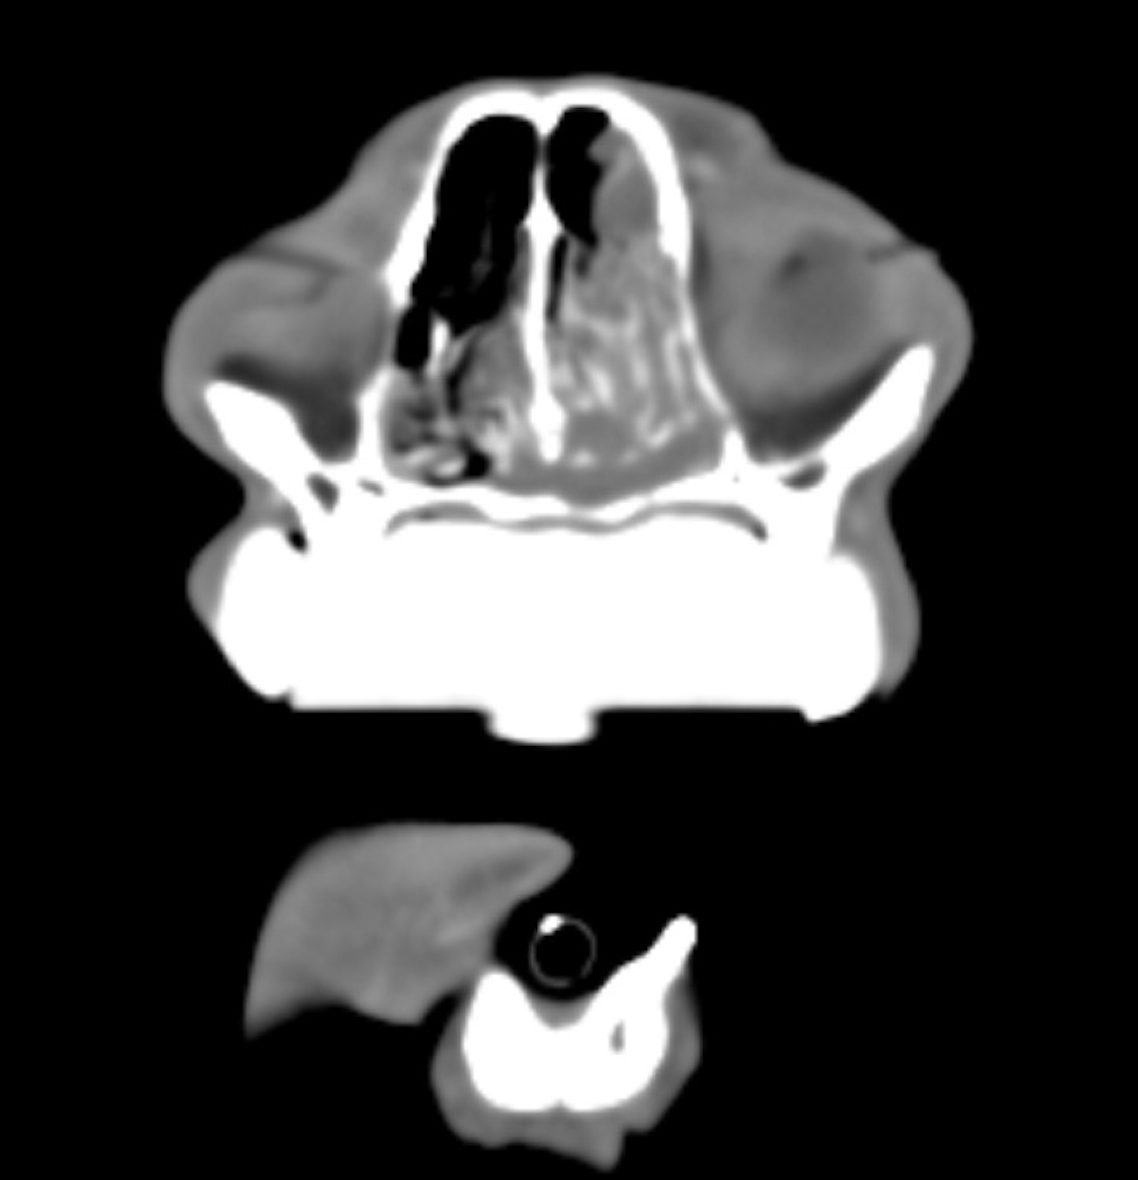

Zur Abklärung der Symptomatik ist zunächst eine Computertomographie mit anschließender Endoskopie geplant. In der Computertomographie zeigt sich der rechte Sinus nasalis im rostralen und mittleren Anteil nahezu vollständig weichteildicht verschattet, nur vereinzelt finden sich rostral Lufteinschlüsse. Der kaudale Bereich ist belüftet, die Lamina cribrosa unverändert. Septum und Conchenstruktur im Bereich der Verschattung sind partiell erhalten. Die Weichteilverschattung nimmt zentral Kontrastmittel auf, setzt sich rostral an den Rändern abgegrenzt in die linke Nasenhöhle fort und wölbt sich von dorsal in den Nasopharynx. Die Lymphknoten zeigen sich unauffällig.

Im vorliegenden Fall ist aufgrund der eindeutigen Befundlage die Strahlentherapie angezeigt, sodass der Patient acht Tage nach der Rhinoskopie und dem Staging (CT Thorax und Abdomenultraschall) zur Planung der Strahlentherapie und Computertomographie vorgestellt wurde. Für die CT wurde, wie bei Nasenhöhlentumoren üblich, eine Vakuummatratze sowie ein Beißkeil angefertigt. Die Strahlentherapie wurde in 10 Fraktionen, werktäglich über zwei Wochen mit einer Gesamtdosis von 42 Gy im Bereich des Primärtumors und mit einer Gesamtdosis von 32 Gy im Bereich der mandibularen und retrophangealen Lymphknoten durchgeführt. Der Patient hat sowohl die Strahlentherapie als auch die Narkosen gut vertragen und wurde bei ungestörtem Allgemeinbefinden entlassen.

Zum aktuellen Zeitpunkt 12 Monate nach Strahlentherapie ist der Kater klinisch in einem guten Allgemeinzustand, die Kontrollen zeigen ein weitgehend normales Bild. Die Besitzer berichten lediglich von gelegentlichem Niesen und intermittierender, geringgradiger Rhinorrhoe. Die Computertomographie 7 Monate nach Strahlentherapie zeigt den Tumor in kompletter Remission und keine relevanten Veränderungen der Nasenhöhlen. Zusammenfassend hat sich der Patient von einem Zustand mit deutlich eingeschränkter Fitness und reduziertem Allgemeinzustand hin zu einem klinisch weitestgehend unauffälligen Kater entwickelt. Zum aktuellen Zeitpunkt spricht nichts für eine absehbare Veränderung und so genießen Besitzer und Patient die aktuelle Situation in vollen Zügen.